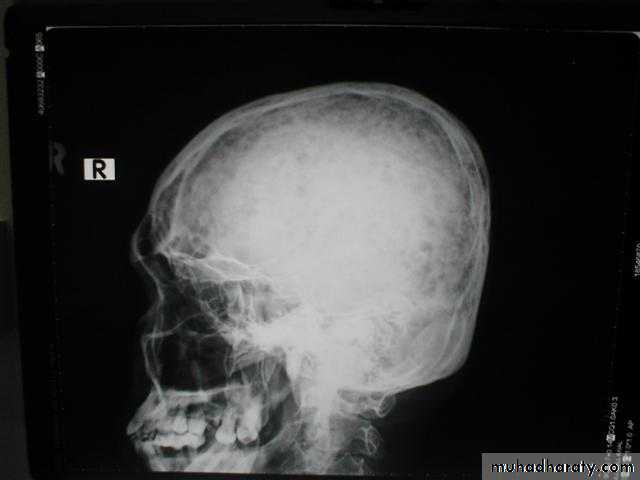

Primary hyperparathyroidism(Radiological features)

Characteristic changes on plane X ray are:

Demineralization, subperiosteal erosion and resorption of terminal phalanges

Pepper pot appearance of the lateral X ray of the skull